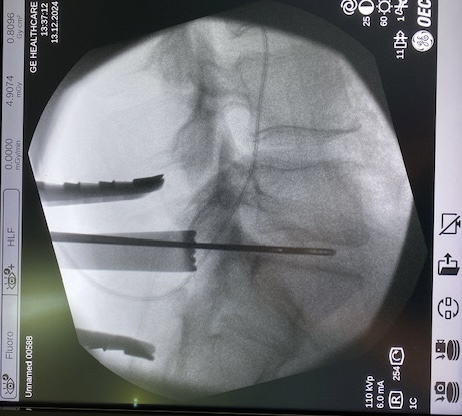

HERNIA DISCAL LUMBAR: en función del caso y las características del paciente, podemos realizar cirugía ENDOSCÓPICA (con unos pequeños orificios y la ayuda de la microcámara eliminamos la hernia discal) o la MICRODISCECTOMIA (una pequeña incisión y la ayuda de un retractor especial para visualización directa y eliminación de la hernia discal). Ambas cirugías tienen una hospitalización corta de 24-48 horas y una recuperación en pocas semanas.

Endoscopia Lumbar